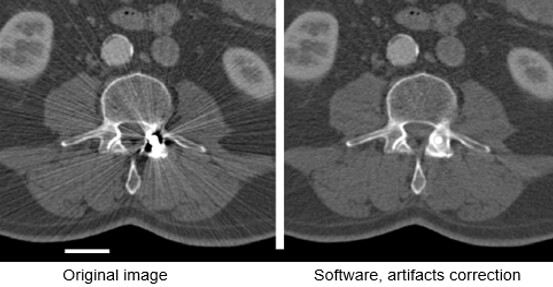

Streaking caused by over ranging can be greatly reduced using special software corrections. Manufacturers use a variety of interpolation techniques designed to substitute the over ranged values in attenuations’ profile.

However, there is always a detail loss around the metal/tissue interface, which is often the area of interest in diagnosis.

This image shows the effectiveness of metal reduction artifact software. Notice how much better the resolution is in the image on the right.